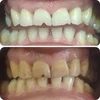

Zirkonyum uygulamalar

Porselen uygulamaları

Laminate veneer